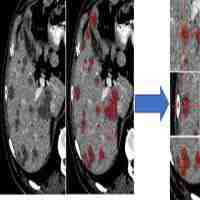

| Abstract | Objective: Liver cancer is one of the most commonly diagnosed cancer, and energy-based tumor ablation is a widely accepted treatment. Automatic and robust segmentation of liver tumors and ablation zones would facilitate the evaluation of treatment success. The purpose of this study was to develop and evaluate an automatic deep learning based method for (1) segmentation of liver and liver tumors in both arterial and portal venous phase for pre-treatment CT, and (2) segmentation of liver and ablation zones in both arterial and portal venous phase for after ablation treatment. Materials and Methods:252 CT images from 63 patients undergoing liver tumor ablation at a large University Hospital were retrospectively included; each patient had pre-treatment and post-treatment multi-phase CT images. 3D voxel-wise manual segmentation of the liver, tumors and ablation region by the radiologist provided reference standard. Deep learning models for liver and lesion segmentation were initially trained on the public Liver Tumor Segmentation Challenge (LiTS) dataset to obtain base models. Then, transfer learning was applied to adapt the base models on the clinical training-set, to obtain tumor and ablation segmentation models both for arterial and portal venous phase images. For modeling, 2D residual-attention Unet (RA-Unet) was employed for liver segmentation and a multi-scale patch-based 3D RA-Unet for tumor and ablation segmentation. Results:On the independent test-set, the proposed method achieved a dice similarity coefficient (DSC) of 0.96 and 0.95 for liver segmentation on arterial and portal venous phase, respectively. For liver tumors, the model on arterial phase achieved detection sensitivity of 71%, DSC of 0.64, and on portal venous phase sensitivity of 82%, DSC of 0.73. For liver tumors >0.5cm3 performance improved to sensitivity 79%, DSC 0.65 on arterial phase and, sensitivity 86%, DSC 0.72 on portal venous phase. For ablation zone, the model on arterial phase achieved detection sensitivity of 90%, DSC of 0.83, and on portal venous phase sensitivity of 90%, DSC of 0.89. Conclusion: The proposed deep learning approach can provide automated segmentation of liver tumors and ablation zones on multi-phase (arterial and portal venous) and multi-time-point (before and after treatment) CT enabling quantitative evaluation of treatment success. |